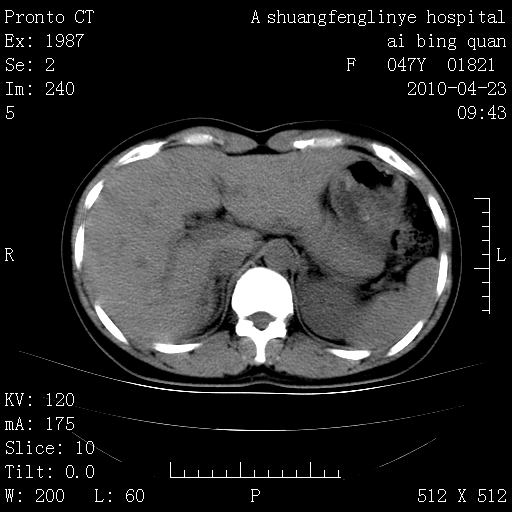

标题: CT25944:胸痛、气短、前几日高烧!肺Ca?请会诊! [打印本页]

标题: CT25944:胸痛、气短、前几日高烧!肺Ca?请会诊!

左侧乳腺低密度灶